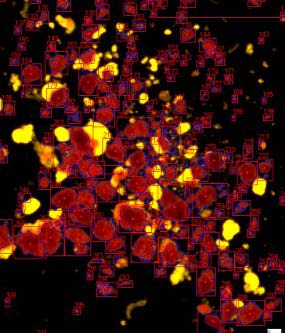

ICC4-230是胰島細(xì)胞自動(dòng)化計(jì)數(shù)儀器:

2. 全新的暗場照明提高了小顆粒檢測、圖像分割的能力,并且可以計(jì)數(shù)純化的未染色樣本;

細(xì)胞自動(dòng)檢測,SNR掃過RGB范圍后的閾值

先進(jìn)的自適應(yīng)分區(qū)算法